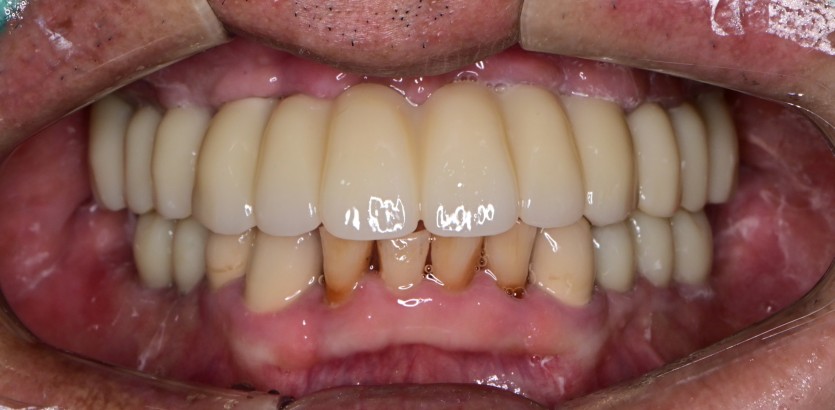

상악 전체 임플란트 / 하악 임플란트 증례입니다.

15개의 임플란트로 완성하였습니다.